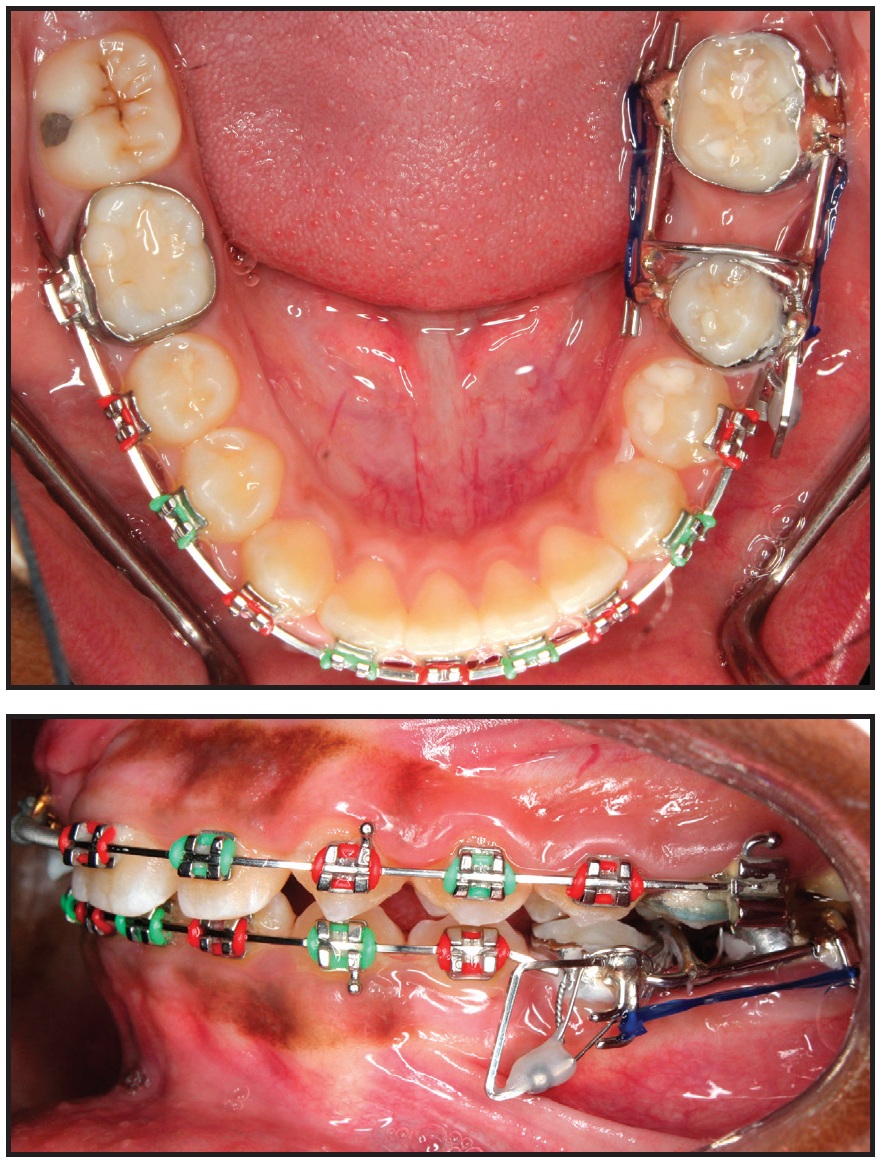

Every six weeks, the appliance was reactivated by attaching new elastomeric chain on both the buccal and lingual sides. The lower left second molar was mesialized in nine months, with only .5mm of anchorage loss of the second premolar (Fig. 9). The appliance was then removed, and a panoramic x-ray indicated that the movement was close to translation. At this point, the buccal segments were in an end-on Class II relationship. A fixed-functional appliance (Forsus Fatigue Resistant Device*) was then delivered to be worn for six months. After the anteroposterior discrepancy was corrected, finishing was carried out with .016" x .022" beta titanium archwires and light seating elastics.

Fig. 9 Lower left second molar mesialized in nine months, with minimal loss of anchorage.

After 37 months of treatment, the orthodontic appliances were removed. A Hawley retainer was fabricated for the maxillary arch, and a 3-3 fixed lingual retainer was bonded in the mandibular arch.

The patient and parents were highly satisfied with the treatment outcome. The impacted upper right central incisor was brought into the arch, the lower left second molar was mesialized to close the missing first-molar space, and the end-on Class II buccal segments on the left side were corrected (Fig. 10A). Cephalometric analysis showed a slight increase in SNB and no change in the vertical dimension (Table 1). The panoramic radiograph and cephalometric superimpositions confirmed an upright lower left second molar in the first-molar space, with the third molar substituting for the second molar (Fig. 10B).